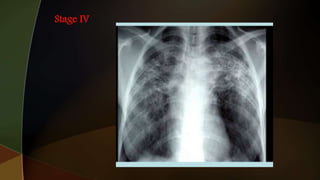

1. hilar adenopathy alone

2. hilar adenopathy plus infiltrates;

3. infiltrates alone;

4. fibrosis

1. hilar adenopathyalone 2. hilar adenopathy plus infiltrates; 3. infiltrates alone; 4. fibrosis